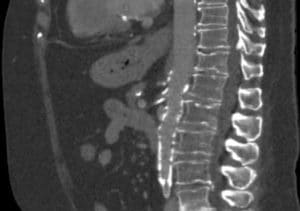

mesenteric artery dissection

Superior mesenteric artery dissection on CT, sagittal view